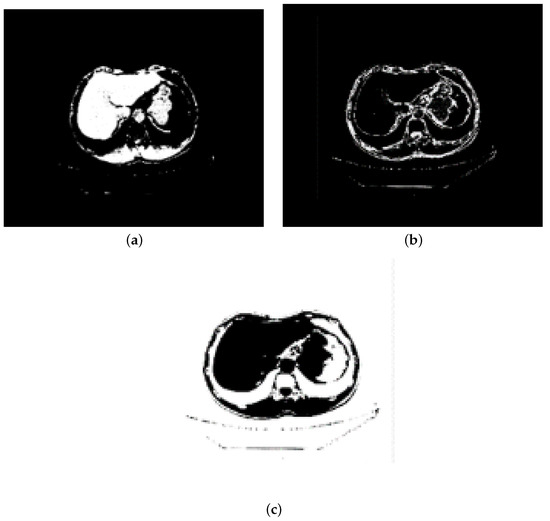

There are artifacts, noise, text information, and other adverse factors in abdominal CT images. Bones, spine, and other organs and tissues whose gray values are similar to those of liver will also affect the segmentation effect. In order to improve the accuracy of segmentation, this paper preprocesses the abdominal CT image: firstly, the image contrast is enhanced by brightness mapping function to reduce the influence of organs and tissues with similar gray values on segmentation. We map the brightness in the gray image to the new value and make 1% of the data have low intensity, high intensity, and saturation. Then, the median filter of 3 × 3 is used to denoise and smooth the image, so as to effectively reduce the artifacts and noise in abdominal CT images, and make the contour of the liver clearer to a certain extent. Finally, we select the threshold according to the distribution of the gray value of the abdominal CT image for threshold segmentation, thus we can remove the parts whose gray value is significantly higher than that of the liver area, such as bone, spine, and text information, and increase the accuracy of the segmented liver image. The T value is set as the threshold. When the gray value is greater than T, we can remove it as spine, rib, and skin, and remove the residual information of the median filter at the same time. When the gray value is between 0 and T, we keep it. The preprocessing process is shown in Figure 2.

Figure 2.

Preprocessing: (a) The original image. (b) The image after contrast enhancement. (c) The image after median filtering. (d) The image after bone and text removal.